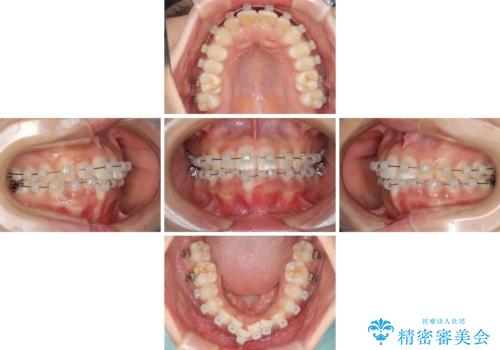

- クリアブラケット

- 治療期間

- 9ヶ月

- 治療回数

- 5-10回